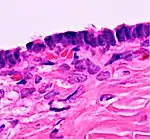

| Functional cyst | Follicular cyst |

|

![]() |

| Corpus luteum cyst |